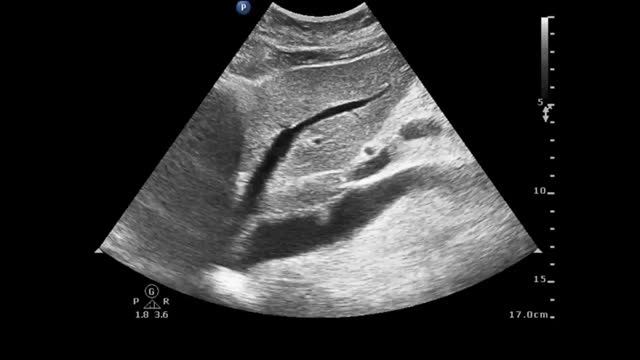

A 35-year-old woman presented to the emergency department with dyspnea and chest tightness lasting for 1 day. Computed tomographic pulmonary angiography confirmed the diagnosis of acute pulmonary embolism (Fig. 1a, yellow arrow). Venovenous extracorporeal membrane oxygenation (VV-ECMO) was implanted due to severe hypoxemia (a P/F ratio of 64 mmHg). Three days later, VV-ECMO was successfully decannulated, and an immediate ultrasound examination detected a rare morphology of ECMO-related thrombus in the inferior vena cava (IVC): a pedunculated, polypoid mobile thrombus floating with a heartbeat (Video 1 and Fig. 1b). The IVC thrombus dissipated after a 3-week standard anticoagulant treatment (Video 2). The case indicated the necessity of routine IVC ultrasound examination after the decannulation of ECMO.